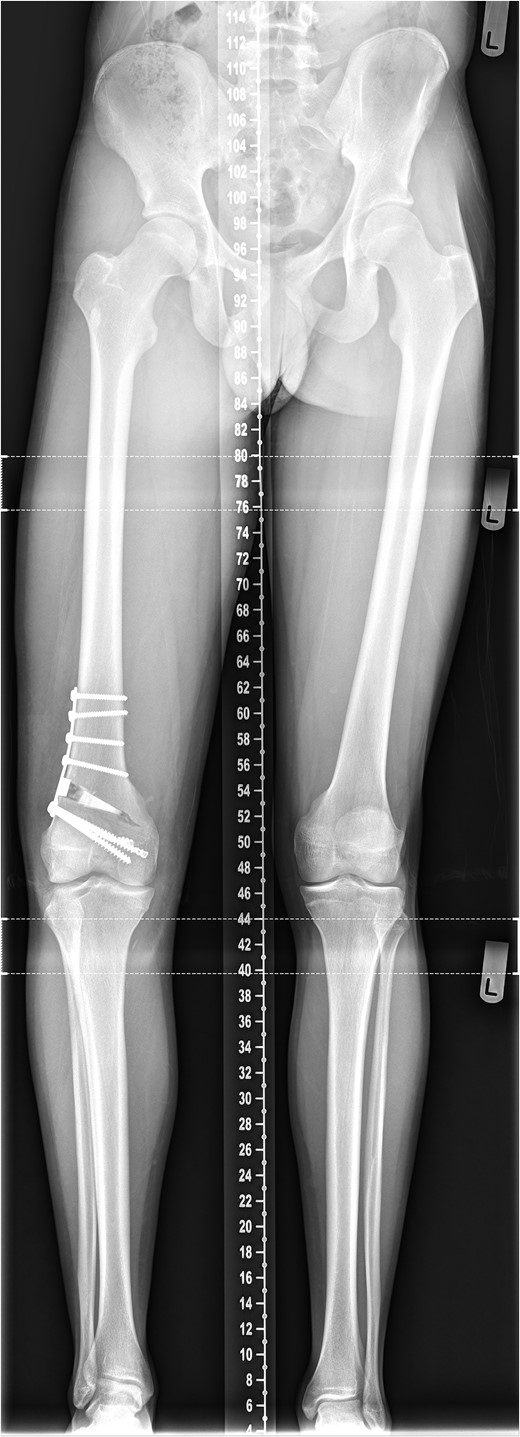

Long-leg alignment radiograph showing valgus deformity of the right knee.

The patient was counseled as to the nature of their injury and the likelihood of ongoing instability and potential for early degenerative change with conservative management. The deformity and instability were successfully treated with an opening distal femoral osteotomy combined with surgical plication of the MCL (Figs 6 and 7). At the time of reporting, 2 years following surgery, the patient has successfully returned to playing competitive football without symptoms of instability. The metalwork remains in situ.